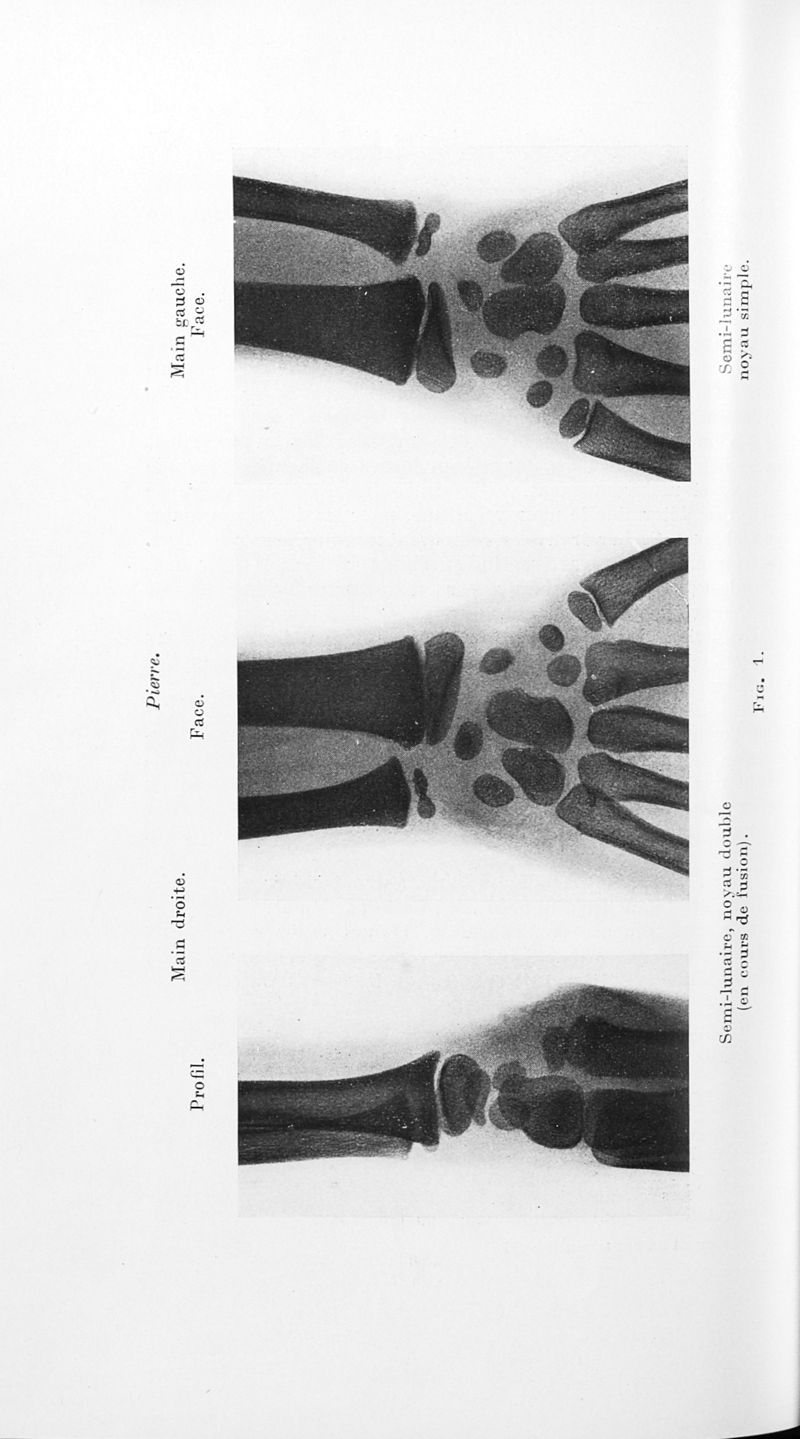

Bulletins de la société de pédiatrie de Paris

Tome trente-sixième. - Paris : Masson et Cie, 1938.